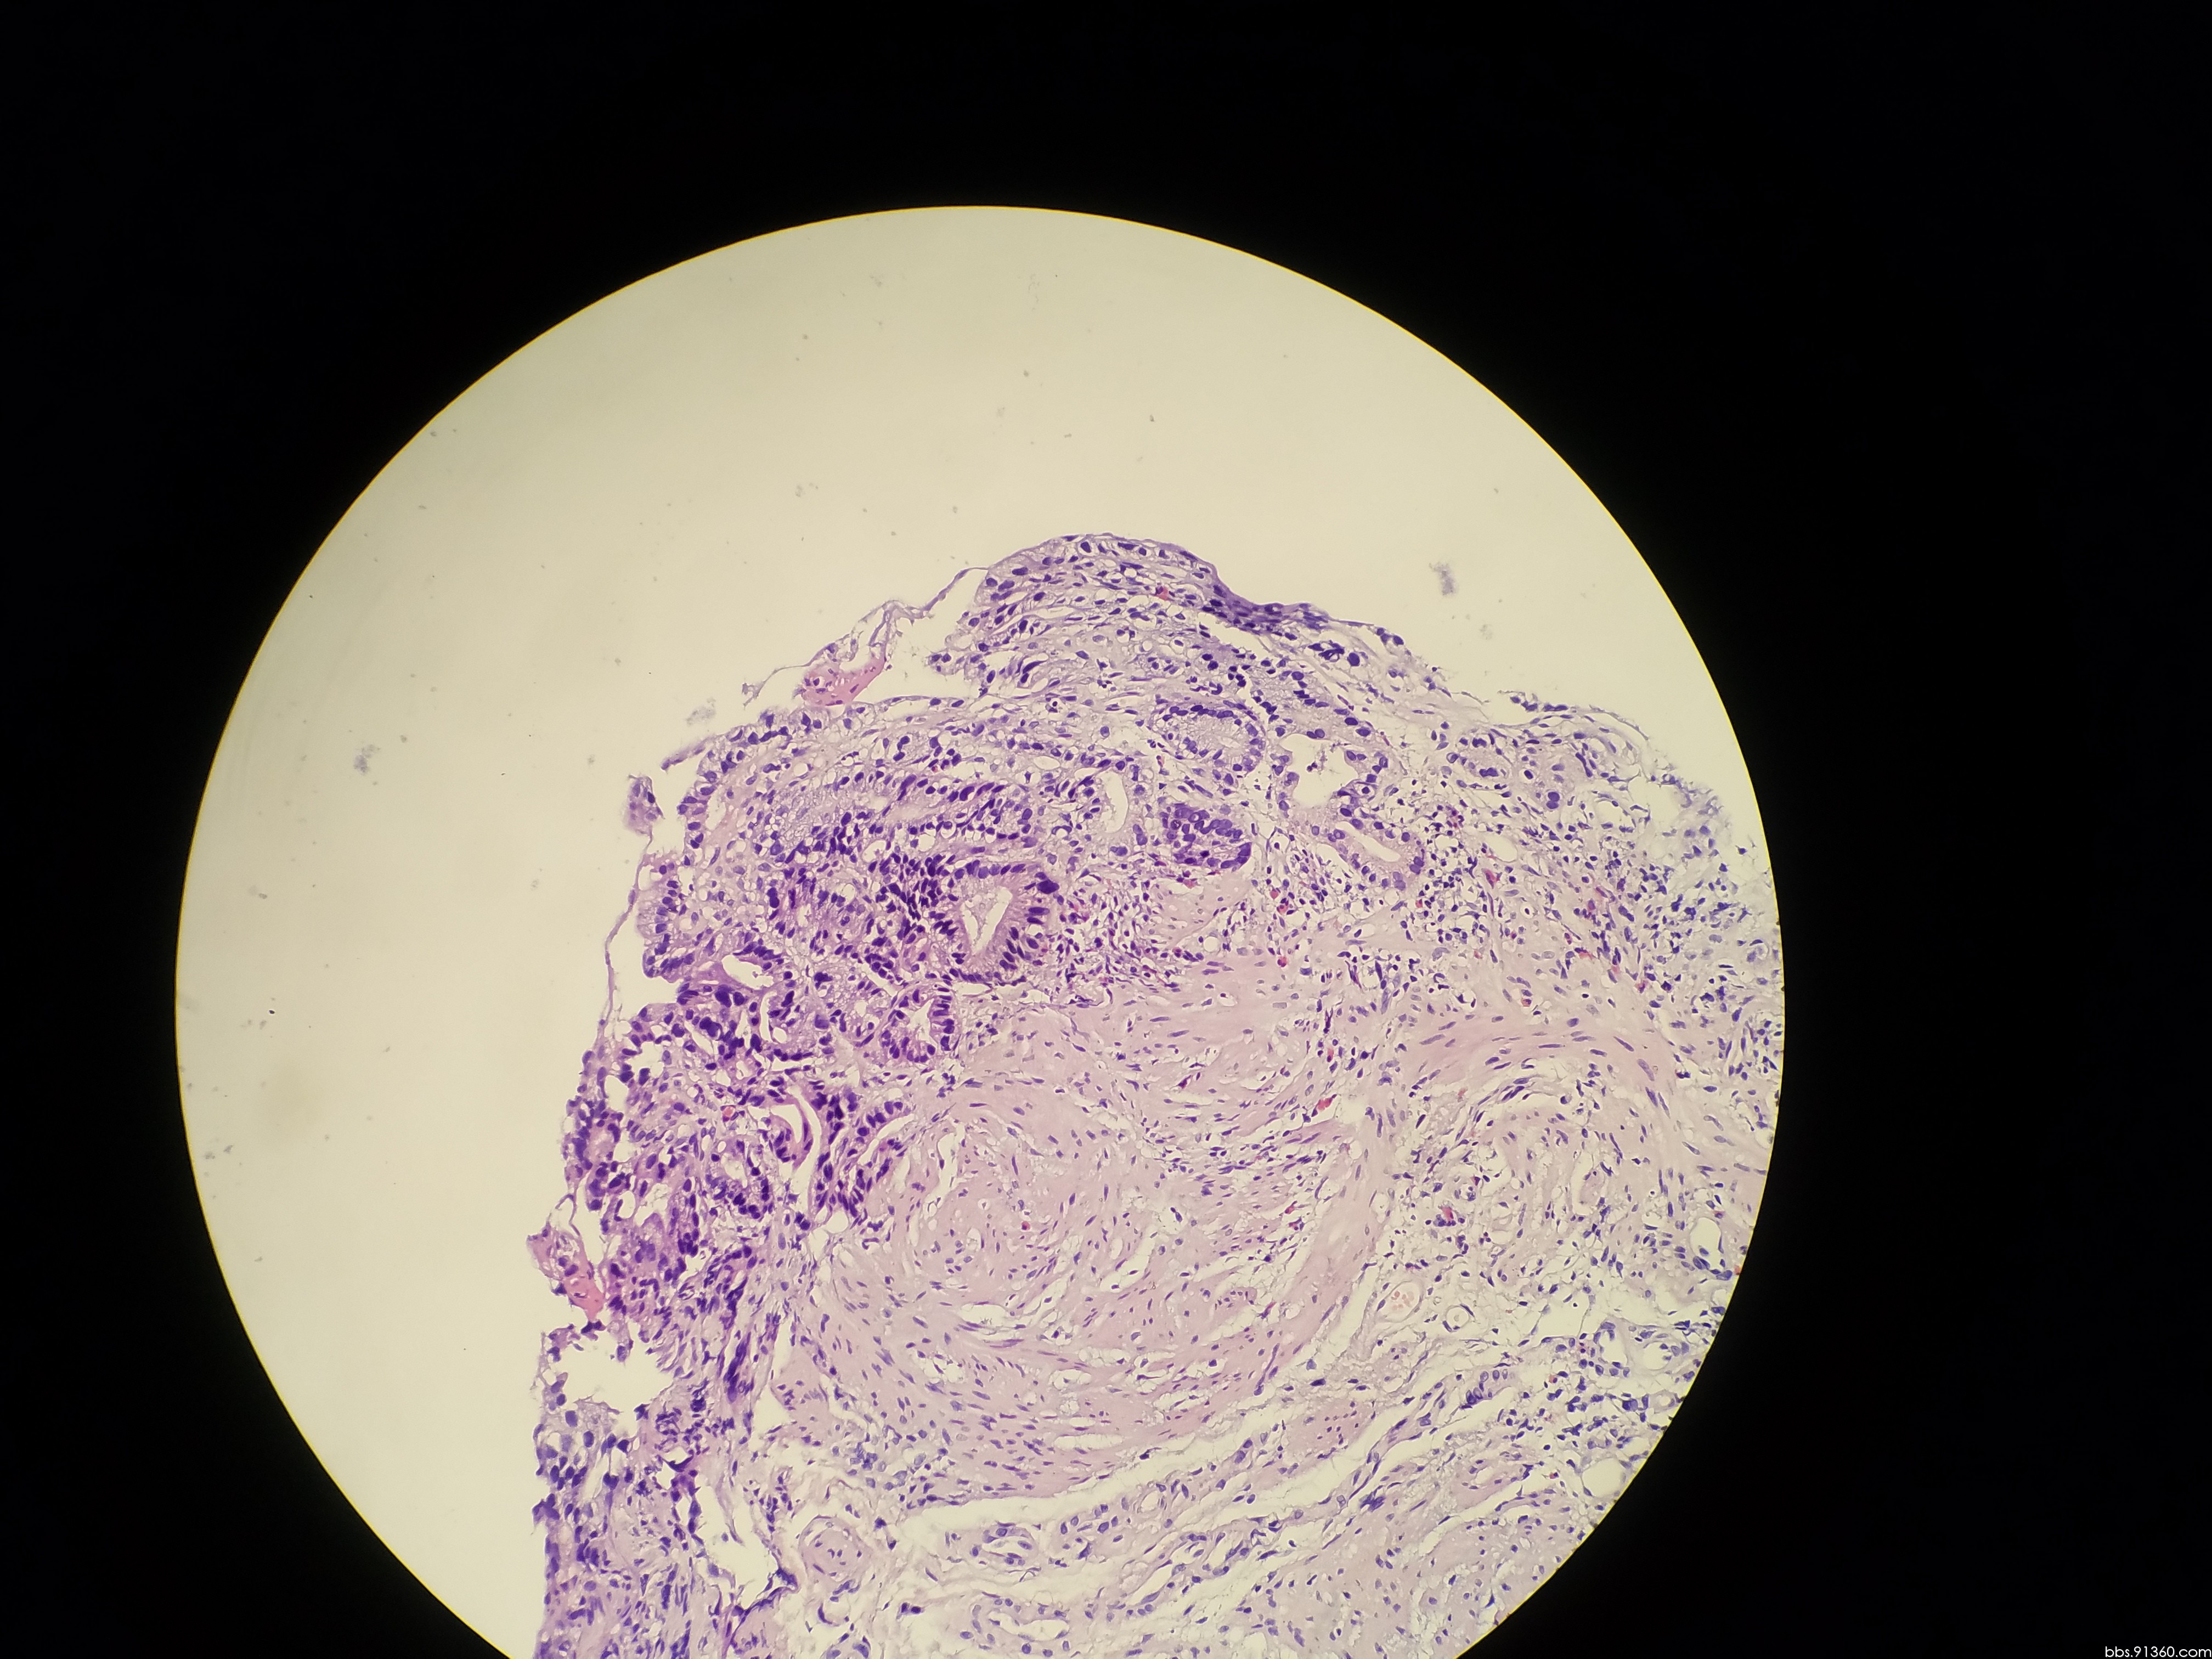

56床陈友文 胃窦腺癌 术前讨论

胃窦部黏膜组织活检镜下如图所示胃黏膜发生的有关病变的描述

胃窦部黏膜组织活检镜下如图所示胃黏膜发生的有关病变的描述错误的是

胃窦粘膜部分腺上皮呈高级别上皮内瘤变